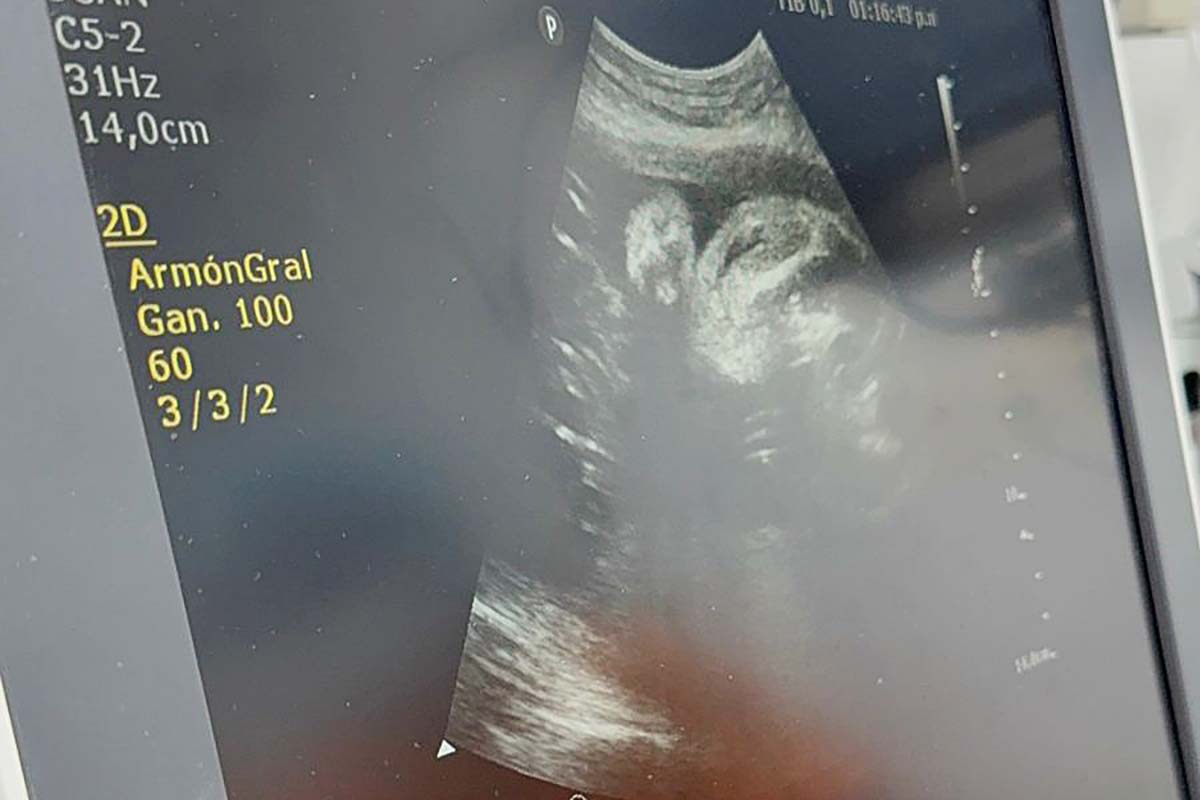

En tanto, el profesional explicó: “Hemos transfundido al niño, para sacarlo del pozo anémico en el que estaba. Tuvimos que hacer un par de procedimientos y está pendiente un tercero, para poder abatir la situación. El procedimiento es simple y complejo a la vez. La parte simple es la función, me guío, pulso, canalizo el cordón umbilical. Y la parte más complicada es todo lo que viene después, porque aquí se involucra no solo el servicio de ecografía, sino por ejemplo el de hematología, que preparan la sangre”.

“Una vez que nosotros hemos canalizado el cordón umbilical, que se va a subir bajo vía ecográfica en quirófano, la técnica requiere mucho entrenamiento, no es fácil, porque primero tenemos que dormir al feto. Hacemos la inyección intramuscular con un preparado especial que se llama vecuronio, fentanilo y atropina. Esa es una dosis, se calcula, con la participación del servicio de anestesia. Colocamos la dosis justa, para que el niño se duerma y se quede quietito, porque no se puede mover y cuando canalizamos el cordón ya que podemos lacerarlo y provocarle la muerte”, relató.

“Posteriormente, tomamos una muestra, mandamos al laboratorio para que nos confirme el grupo sanguíneo y el hematocrito, o la hemoglobina, para ver cuán anímico está o no. En base a eso, tenemos otros dos ayudantes que cada uno hace los cálculos por separado, para ver si coinciden. Calculan en base a los centígrados que lleva la bolsa a transfundir, más los glóbulos rojos que lleva el feto, se hace un cálculo del volumen, todos ellos hacen a la vez, mientras que yo voy canalizando, mando al laboratorio, hay dos chicos que están con el programa abierto, un asistente que corre al laboratorio, me trae automáticamente la concentración de sangre del feto, mientras tanto voy transfundiendo de a poco, ambos chicos hacen los cálculos matemáticos en mi programa especial y tienen que coincidir. Y empezamos a transfundirlo. Inmediatamente, antes de sacar la aguja, limpiamos con fisiológica y tomamos otra muestra para ver el hematocrito o la constelación de sangre post procedimiento”, relató.